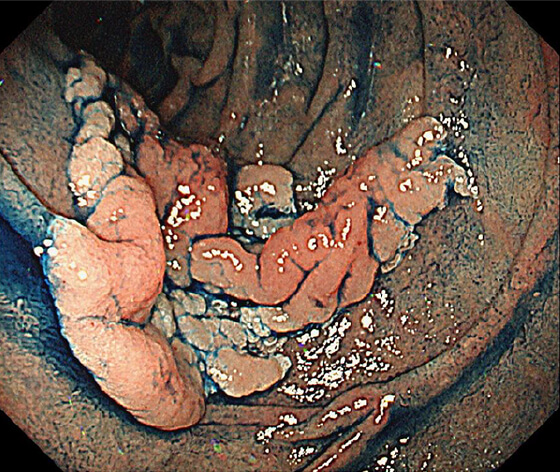

光線力学的療法(PDT)

放射線療法後の遺残再発食道癌に対する光線力学的療法(PDT)も行っており、PDTの実施可能施設は九州で4施設のみ、長崎県内では当院が唯一の実施施設となっています。